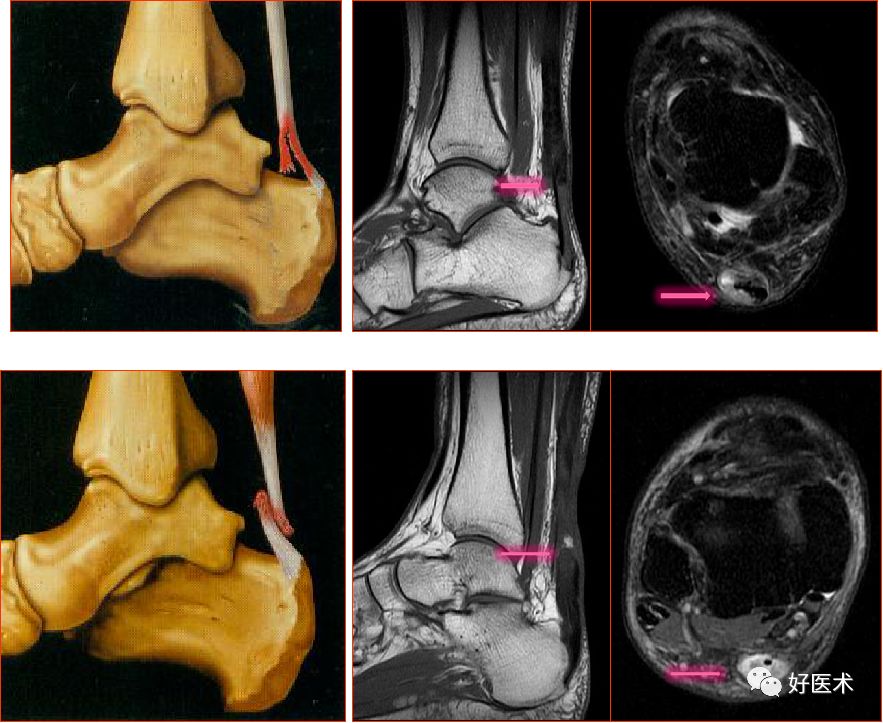

外侧副韧带

距腓前韧带

距腓前韧带撕裂

距腓后韧带

距腓后韧带部分撕裂

跟腓韧带

跟腓韧带急性完全撕裂